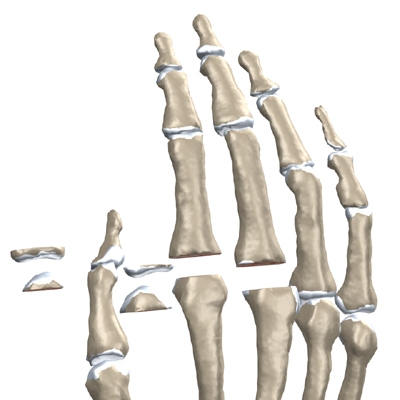

The finger joints work like hinges when they bend and straighten. The main knuckle joint is the metacarpophalangeal joint (MCP joint). It is formed by the connection of the metacarpal bone in the palm of the hand to the finger bone, or phalange. Each finger (the thumb is not termed a finger) has three phalanges, separated by two interphalangeal joints (IP joints). The one closest to the MCP joint (knuckle) is called the proximal IP joint (PIP joint). The joint near the end of the finger is called the distal IP joint (DIP joint).

An incision is made across the back of the finger joints that are to be replaced. The soft tissues are spread apart with a retractor. Special care is taken not to damage the nearby nerve that passes by the joint. The joint is exposed. The ends of the bones that form the finger joint surfaces are taken off, forming flat surfaces.

A burr (a small cutting tool) is used to make a canal into the bones that form the finger joint.

The surgeon then sizes the stem of the prosthesis to ensure a snug fit into the hollow bone marrow space of the bone. The prosthesis is inserted into the ends of both finger bones.